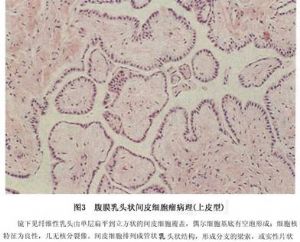

(2)上皮样间皮瘤:上皮样间皮瘤瘤细胞呈立方形或多角形,常有脉管状或乳头状结构。上皮性间皮瘤最多见于弥漫性间皮瘤中,瘤细胞呈不同的分化状态,可形成高分化管状或乳头状结构,也可呈未分化的片块状瘤组织,瘤细胞大小不一,呈实性,为结缔组织所包绕。管状乳头状结构的瘤组织构成腺样、管状或者囊性,内衬以立方或扁平的上皮样细胞,细胞大小一致,空泡状核,可见1~2个核仁。胞浆丰富,细胞轮廓清楚。肿瘤亦可呈裂隙状或形成大小不等的囊腔,内衬以扁平的上皮细胞,这些裂隙内有时可见乳头状突起。类似乳头状腺癌。有些病例,瘤细胞排列成实性、条索状或者巢状,无腺样或乳头状结构。但有时瘤组织周围可有黏液物质,形成类似黏液湖的结构。细胞形态比较一致,核大小不一,胞浆内时有空泡形成,含有黏多糖类物质(图3)。

(2)上皮样间皮瘤:上皮样间皮瘤瘤细胞呈立方形或多角形,常有脉管状或乳头状结构。上皮性间皮瘤最多见于弥漫性间皮瘤中,瘤细胞呈不同的分化状态,可形成高分化管状或乳头状结构,也可呈未分化的片块状瘤组织,瘤细胞大小不一,呈实性,为结缔组织所包绕。管状乳头状结构的瘤组织构成腺样、管状或者囊性,内衬以立方或扁平的上皮样细胞,细胞大小一致,空泡状核,可见1~2个核仁。胞浆丰富,细胞轮廓清楚。肿瘤亦可呈裂隙状或形成大小不等的囊腔,内衬以扁平的上皮细胞,这些裂隙内有时可见乳头状突起。类似乳头状腺癌。有些病例,瘤细胞排列成实性、条索状或者巢状,无腺样或乳头状结构。但有时瘤组织周围可有黏液物质,形成类似黏液湖的结构。细胞形态比较一致,核大小不一,胞浆内时有空泡形成,含有黏多糖类物质(图3)。